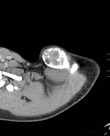

Пришли результаты анализа пробы опухоли из Берлина.

Берлинска лаборатория говорит, что это и не опухоль вовсе, а киста.

А значит операция должна пройти совсем по- другому...